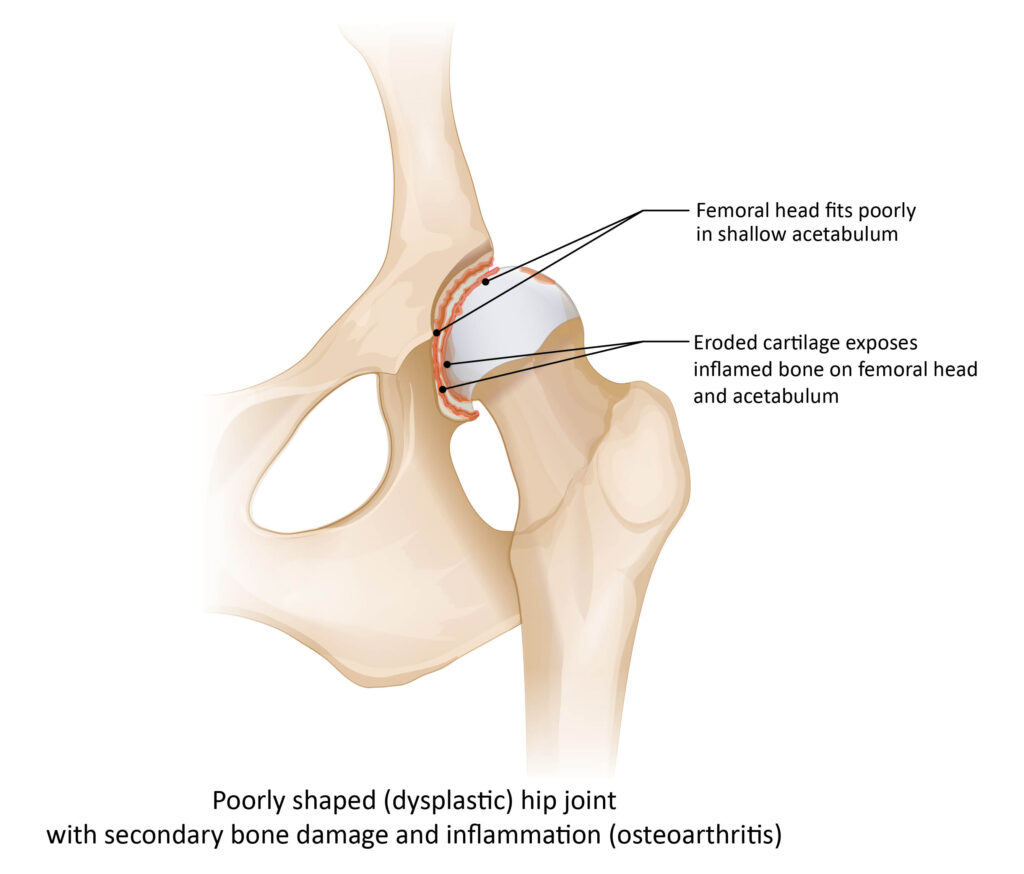

La dysplasie coxo-fémorale (HD) est une anomalie de développement de l’articulation de la hanche, liée à une mauvaise conformation de la hanche : la tête du fémur s’emboîte mal dans la cavité de la hanche, associée à un relâchement du ligament qui les unit. Cette anomalie créée à terme une dégénérescence articulaire et des lésions progressives des cartilages, des ligaments et des os qui la constituent. La malformation peut passer inaperçue à la naissance, et se manifester lors de la croissance, durant laquelle des modifications articulaires apparaissent, pouvant mener à une coxarthrose douloureuse et handicapante.

L’examen radiologique permet de mettre en évidence des signes d’arthrose ainsi que de mesurer l’angle de NORBERG-OLSSON, qui donne une idée de la couverture de la tête par l’acétabulum et de la pénétration de la tête au fond de la cavité acétabulaire.